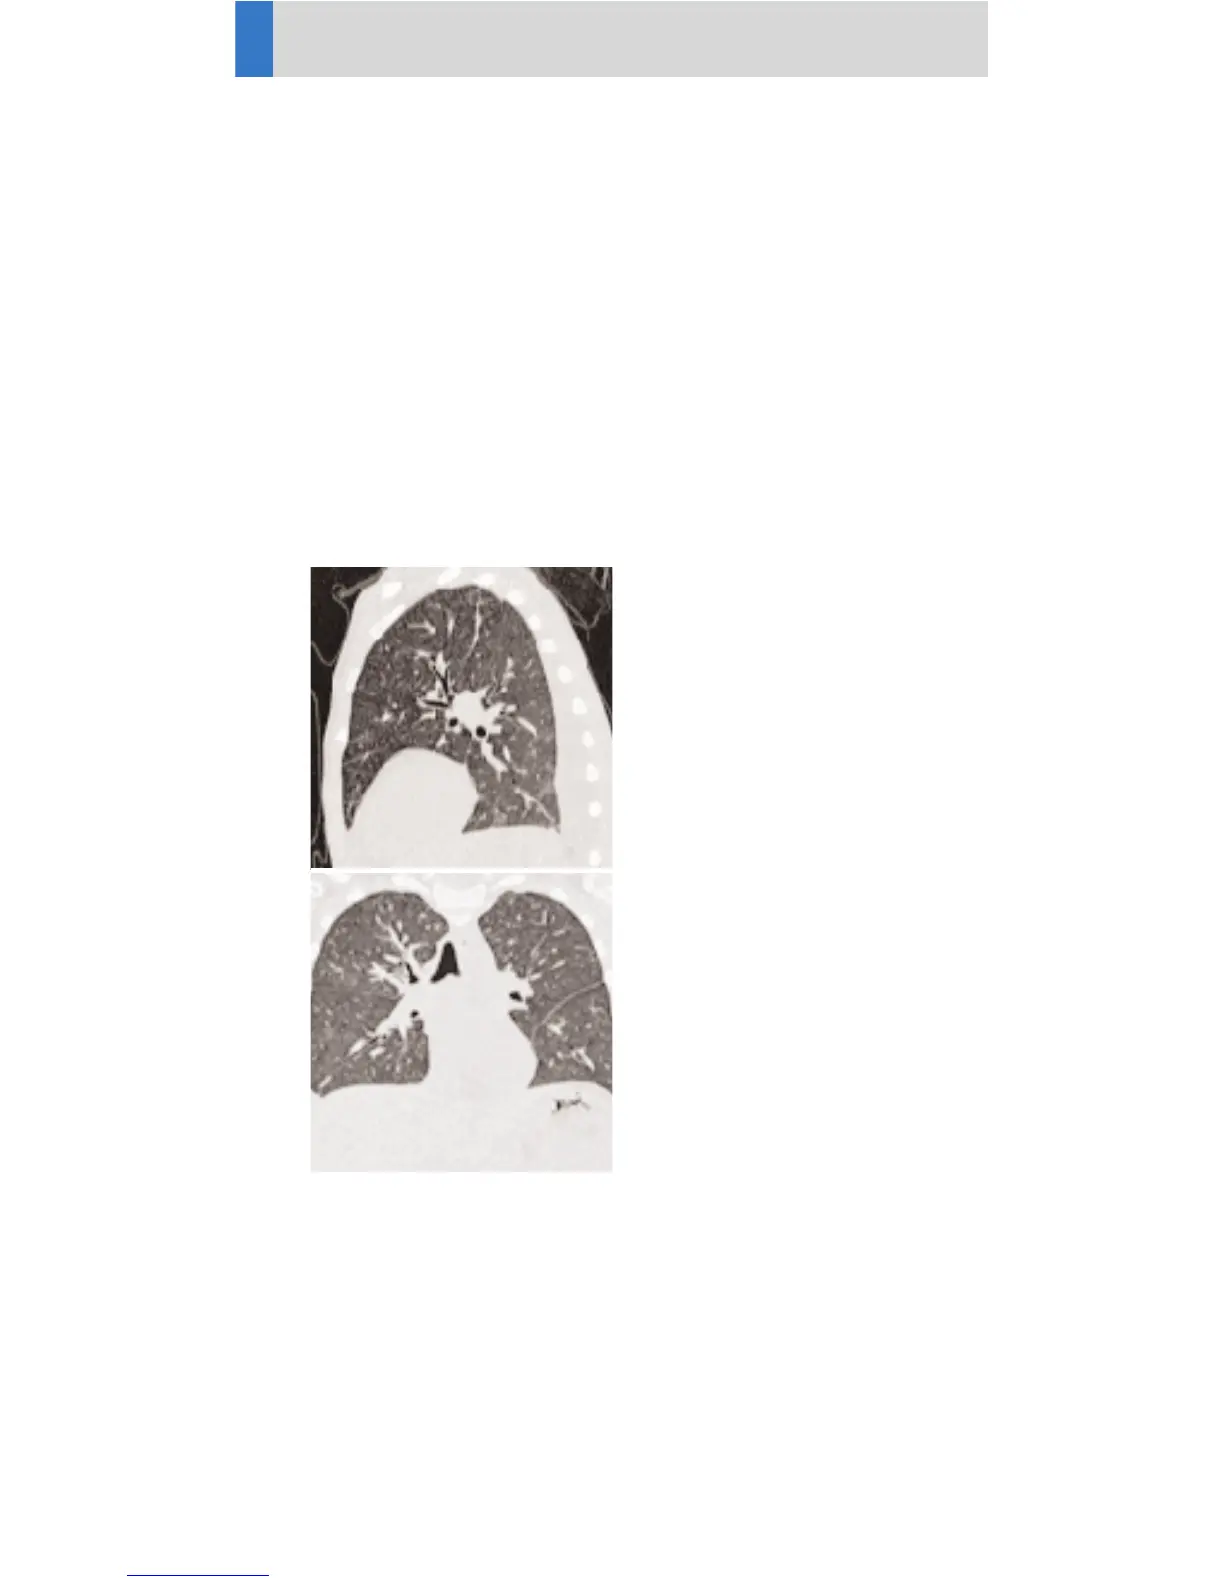

ThoraxCombi

Indications:

Combining thin slice lung and routine thorax studies

with one spiral scan. E. g. thorax studies in general and

interstitial changes in the lungs. There are two recon

jobs predefined. The first one, with 3 mm slice thick-

ness, for the mediastinum, the second reconstruction,

with 1.25 mm slice thickness, for the lung.

A range of 15 cm will be covered in 15 sec.